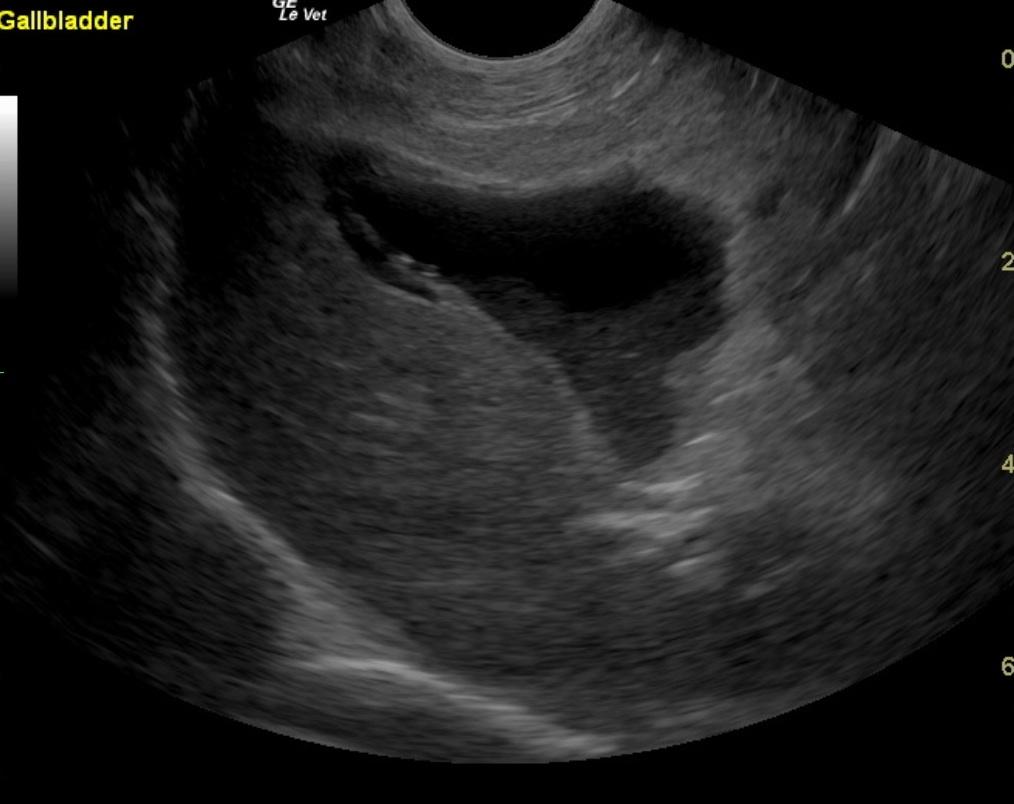

A 7-year-old FS Jack Russell Terrier with a history of regulated hypothyroidism, was presented for vomiting, lateral recumbency, and abdominal pain following ingestion of a ham bone. The owner also reported that the patient had been showing polyuria/polydipsia prior to the incident. On physical examination, the patient was laterally recumbent and very painful. CBC showed polycythemia and low band neutrophils. On blood chemistry, mildly elevated BUN, elevated creatinine, elevated ALP activity, elevated lipase, severely elevated ALT activity, and elevated cPLI were evident. A hemorrhagic diathesis was present on coagulation panel. Blood pressure was 145/80. The patient was treated with I.V. fluids, hetastarch, morphine/ketamine drip, fresh frozen plasma, antibiotics, and placed in an oxygen cage. On survey abdominal radiographs, bony fragments were evident in the gastrointestinal tract. The patient was sedated, given an enema, and a large piece of bone was produced. After 42 hours on therapy the patient developed dyspnea, which, on survey thoracic radiographs, was suggestive of fluid overload. Lasix was administered, which resulted in resolution of the dyspnea. Recheck blood chemistry showed hypoproteinemia, elevated ALP activity, hyperglycemia, improved azotemia, and normalization of cPLI. Physical examination, after 72 hours of supportive care, found the patient BAR and ambulatory, not interested in food, and still extremely painful upon palpation of the right mid-abdomen. Syringe feedings were started, which were well tolerated with no vomiting. However, the following morning the patient was less bright and more painful in the abdomen.